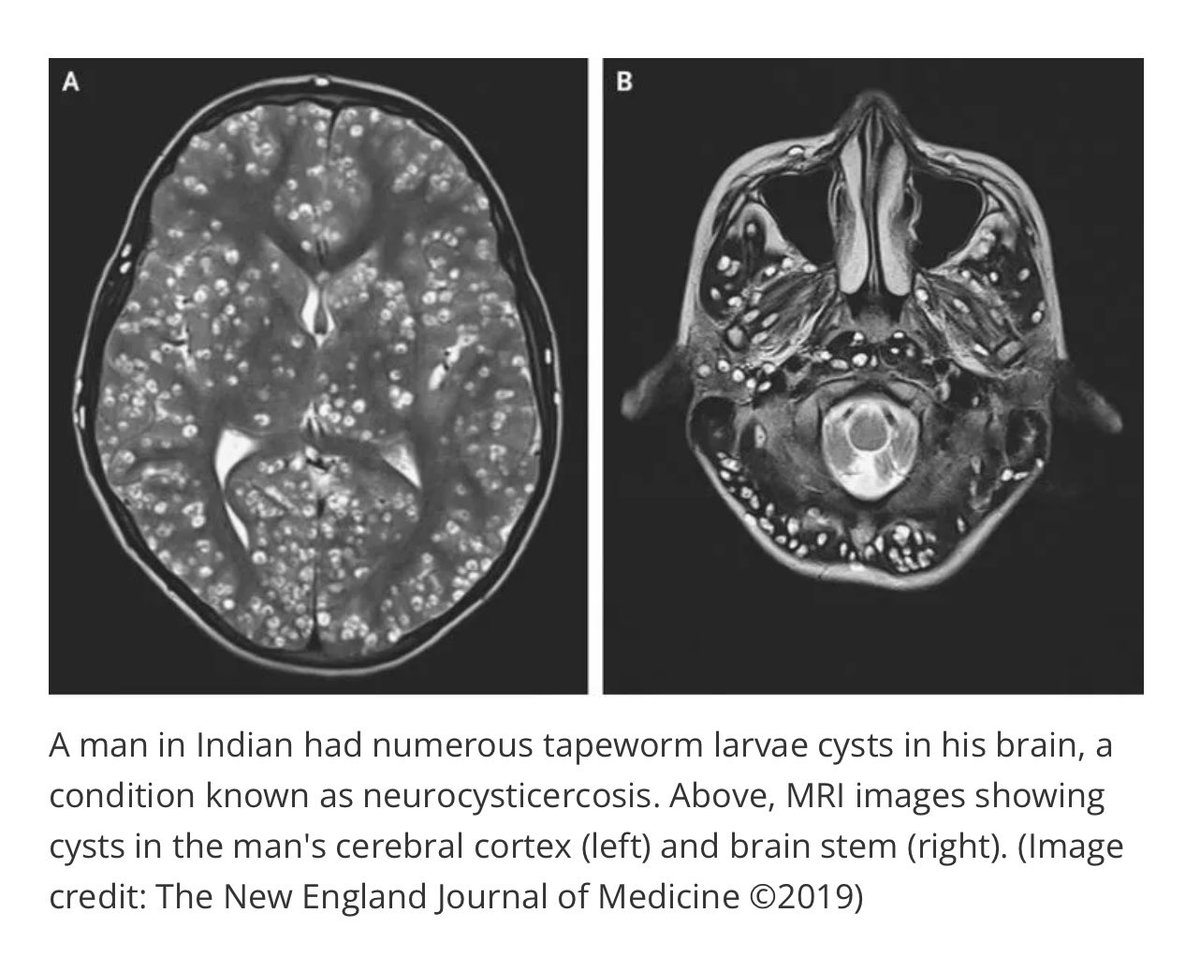

Kasus yang Bikin Merinding